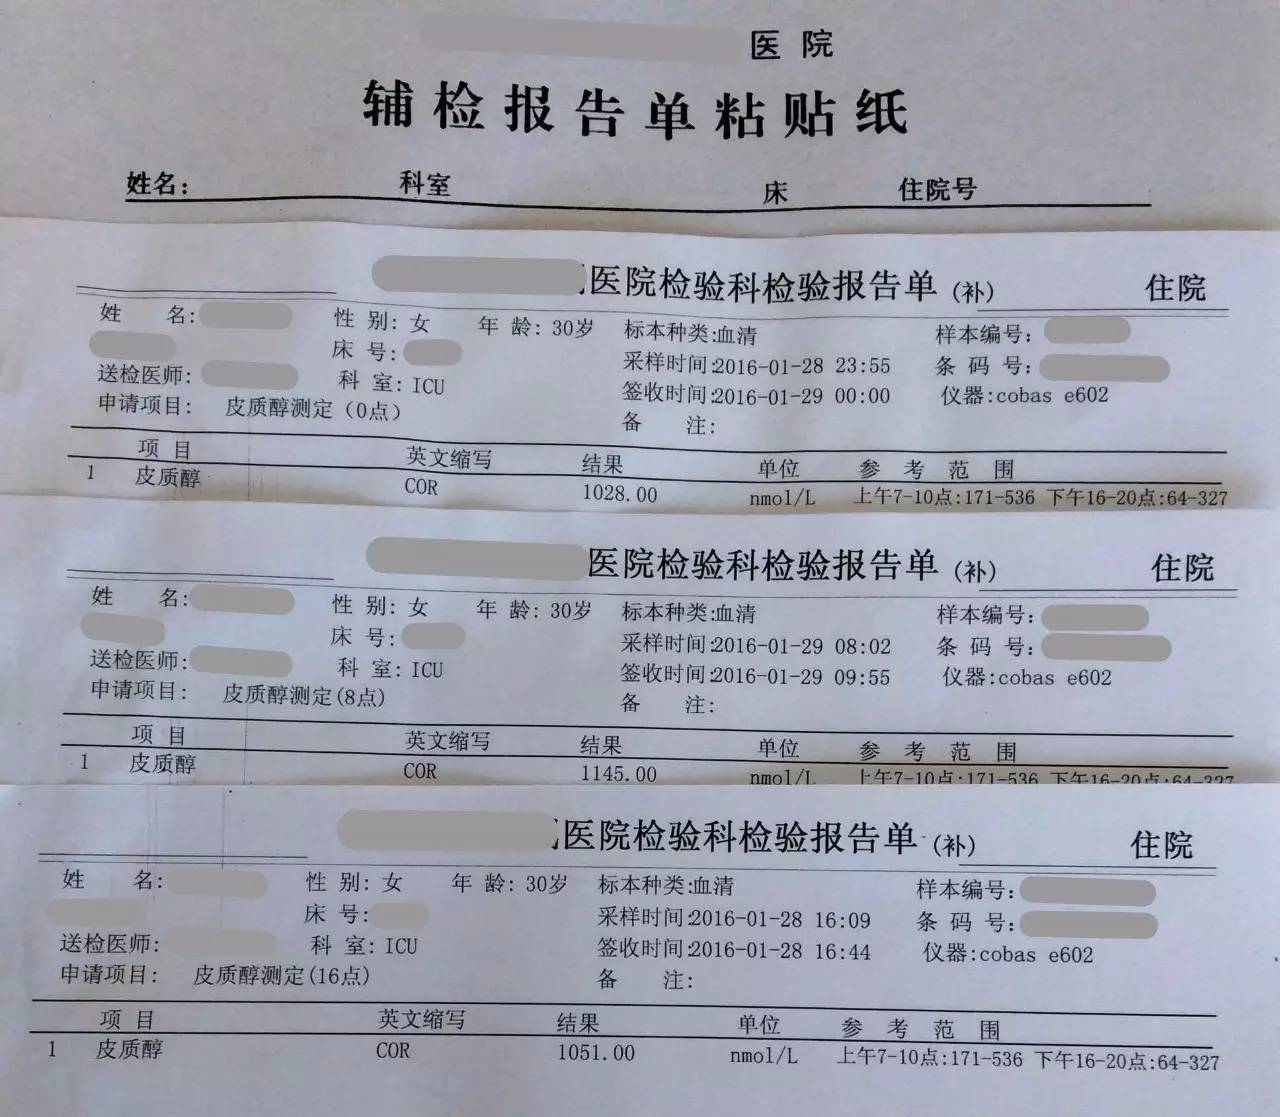

▼患者检查报告资料

目前患者面临的问题是出现了甲状腺功能减退症和肾上腺激素需要减量的问题。结合患者产后一系列的意外和抢救过程,要警惕患者出现Sheehan syndrome(希恩综合征),因为低血压、出血等等引起垂体缺血缺氧所致。

2.患者应用甲强龙,当时是因为出现了休克为了抢救所用,目前情况明细好转,可以每周(也就是贵院内分泌大夫会诊的7~10天)减量甲强龙1片(4mg); 但因为患者可能存在继发性肾上腺皮质功能减退症(继发于希恩综合征),减量到全天2片时需要评估清晨未服药前ACTH和血皮质醇、电解质、性腺激素六项来评估是否能够完全停药,还是需要减成替代剂量,此时可以应用泼尼松来替代甲强龙,泼尼松一片是5mg,等效于甲强龙1片,4mg,如果确实出现肾上腺皮质功能减退,可以逐渐减量到泼尼松全天1片(2.5mg,早上和下午各服用一片)。到时候再根据患者复查的情况判断肾上腺功能的恢复情况。